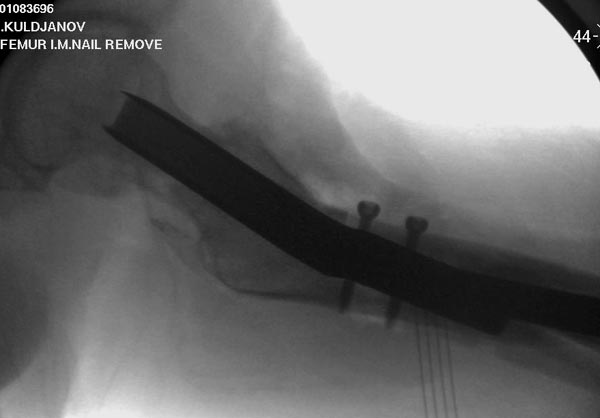

Здесь выставлен ренгенограммы больного, ему 21, травму получил в

результате высокоскоростной погони на украденной машине, которая

закончилась смертью трех остальных“боевых комрадов”. Начатую коллегой

открытую операцию на шейке пришлось закончить мне, установкой винтов и

ретроградной фиксацией бедра. Выписка в обычное сроки и наблюдался

амбулаторно. Каждый раз напоминали о возможности осложнений ввиде

несращения! По истечению 4 месяцев появились признаки варусной

деформации. На СТ срезах несращение шейки и бедра. Риминг, замена на

более толстый гвоздь и вальгусная остеотомия.